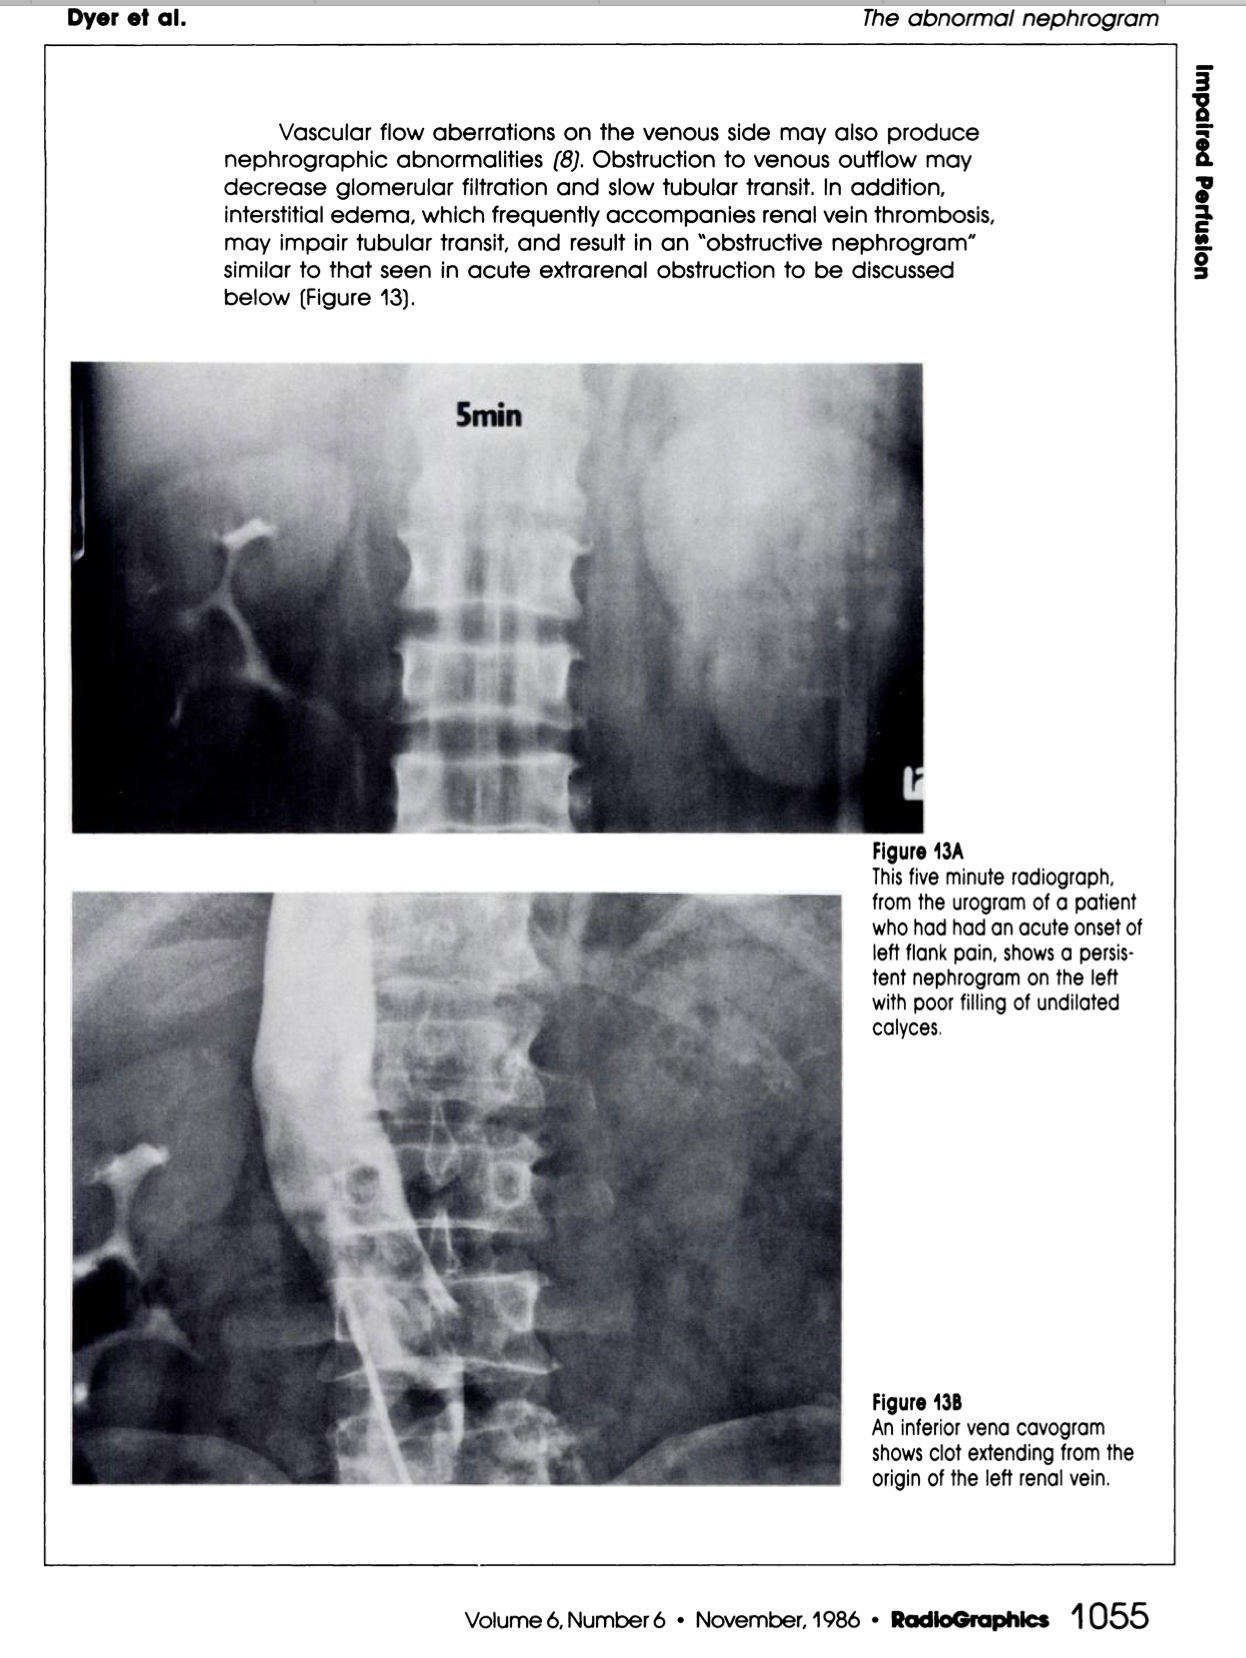

What are the signs of RVT on IVP?

What sign is this?

Delayed nephrogram

IVP:

https://pubs.rsna.org/doi/pdf/10.1148/radiographics.6.6.3685518